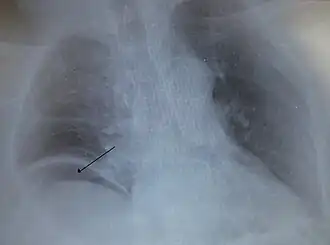

Aire libre bajo el diafragma derecho desde un intestino perforado.